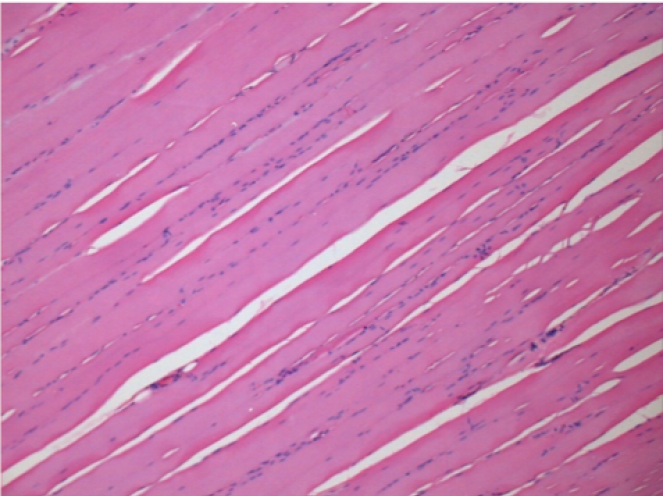

09

7 mesi dopo Iniezione di Endopeel

Scatola Nr 5

7 mesi (Giorno210) dopo iniezione IM di 0.1ml di Endopeel nel muscolo pretibiale destro ( Dx).

Restitutio ad integrum completo dopo 7 mesi

Sx : Controllo-100x-Giorno210

Dx:100x-Giorno210

Sx :Controllo 50x-Giorno210

Dx:50X-Giorno210